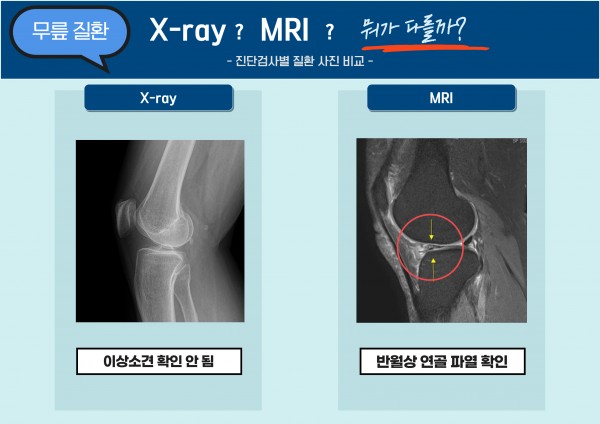

엑스레이상에서는 손상이 보이지 않아도 MRI에서는 뼈에 멍이 든 것 같이 미세골절이 발견되기도 하고,

특히 작은 혈관, 신경, 연골이나 힘줄 손상은 고해상도 MRI로만 확인이 가능하기 때문입니다.

때문에 정형외과 전문의가 환자분에게 MRI 촬영을 요청하는 경우는

엑스레이상의 이상소견이나 의심소견이 있고 더욱 정확한 진단과 최적의 치료법을 제공하기 위함입니다.